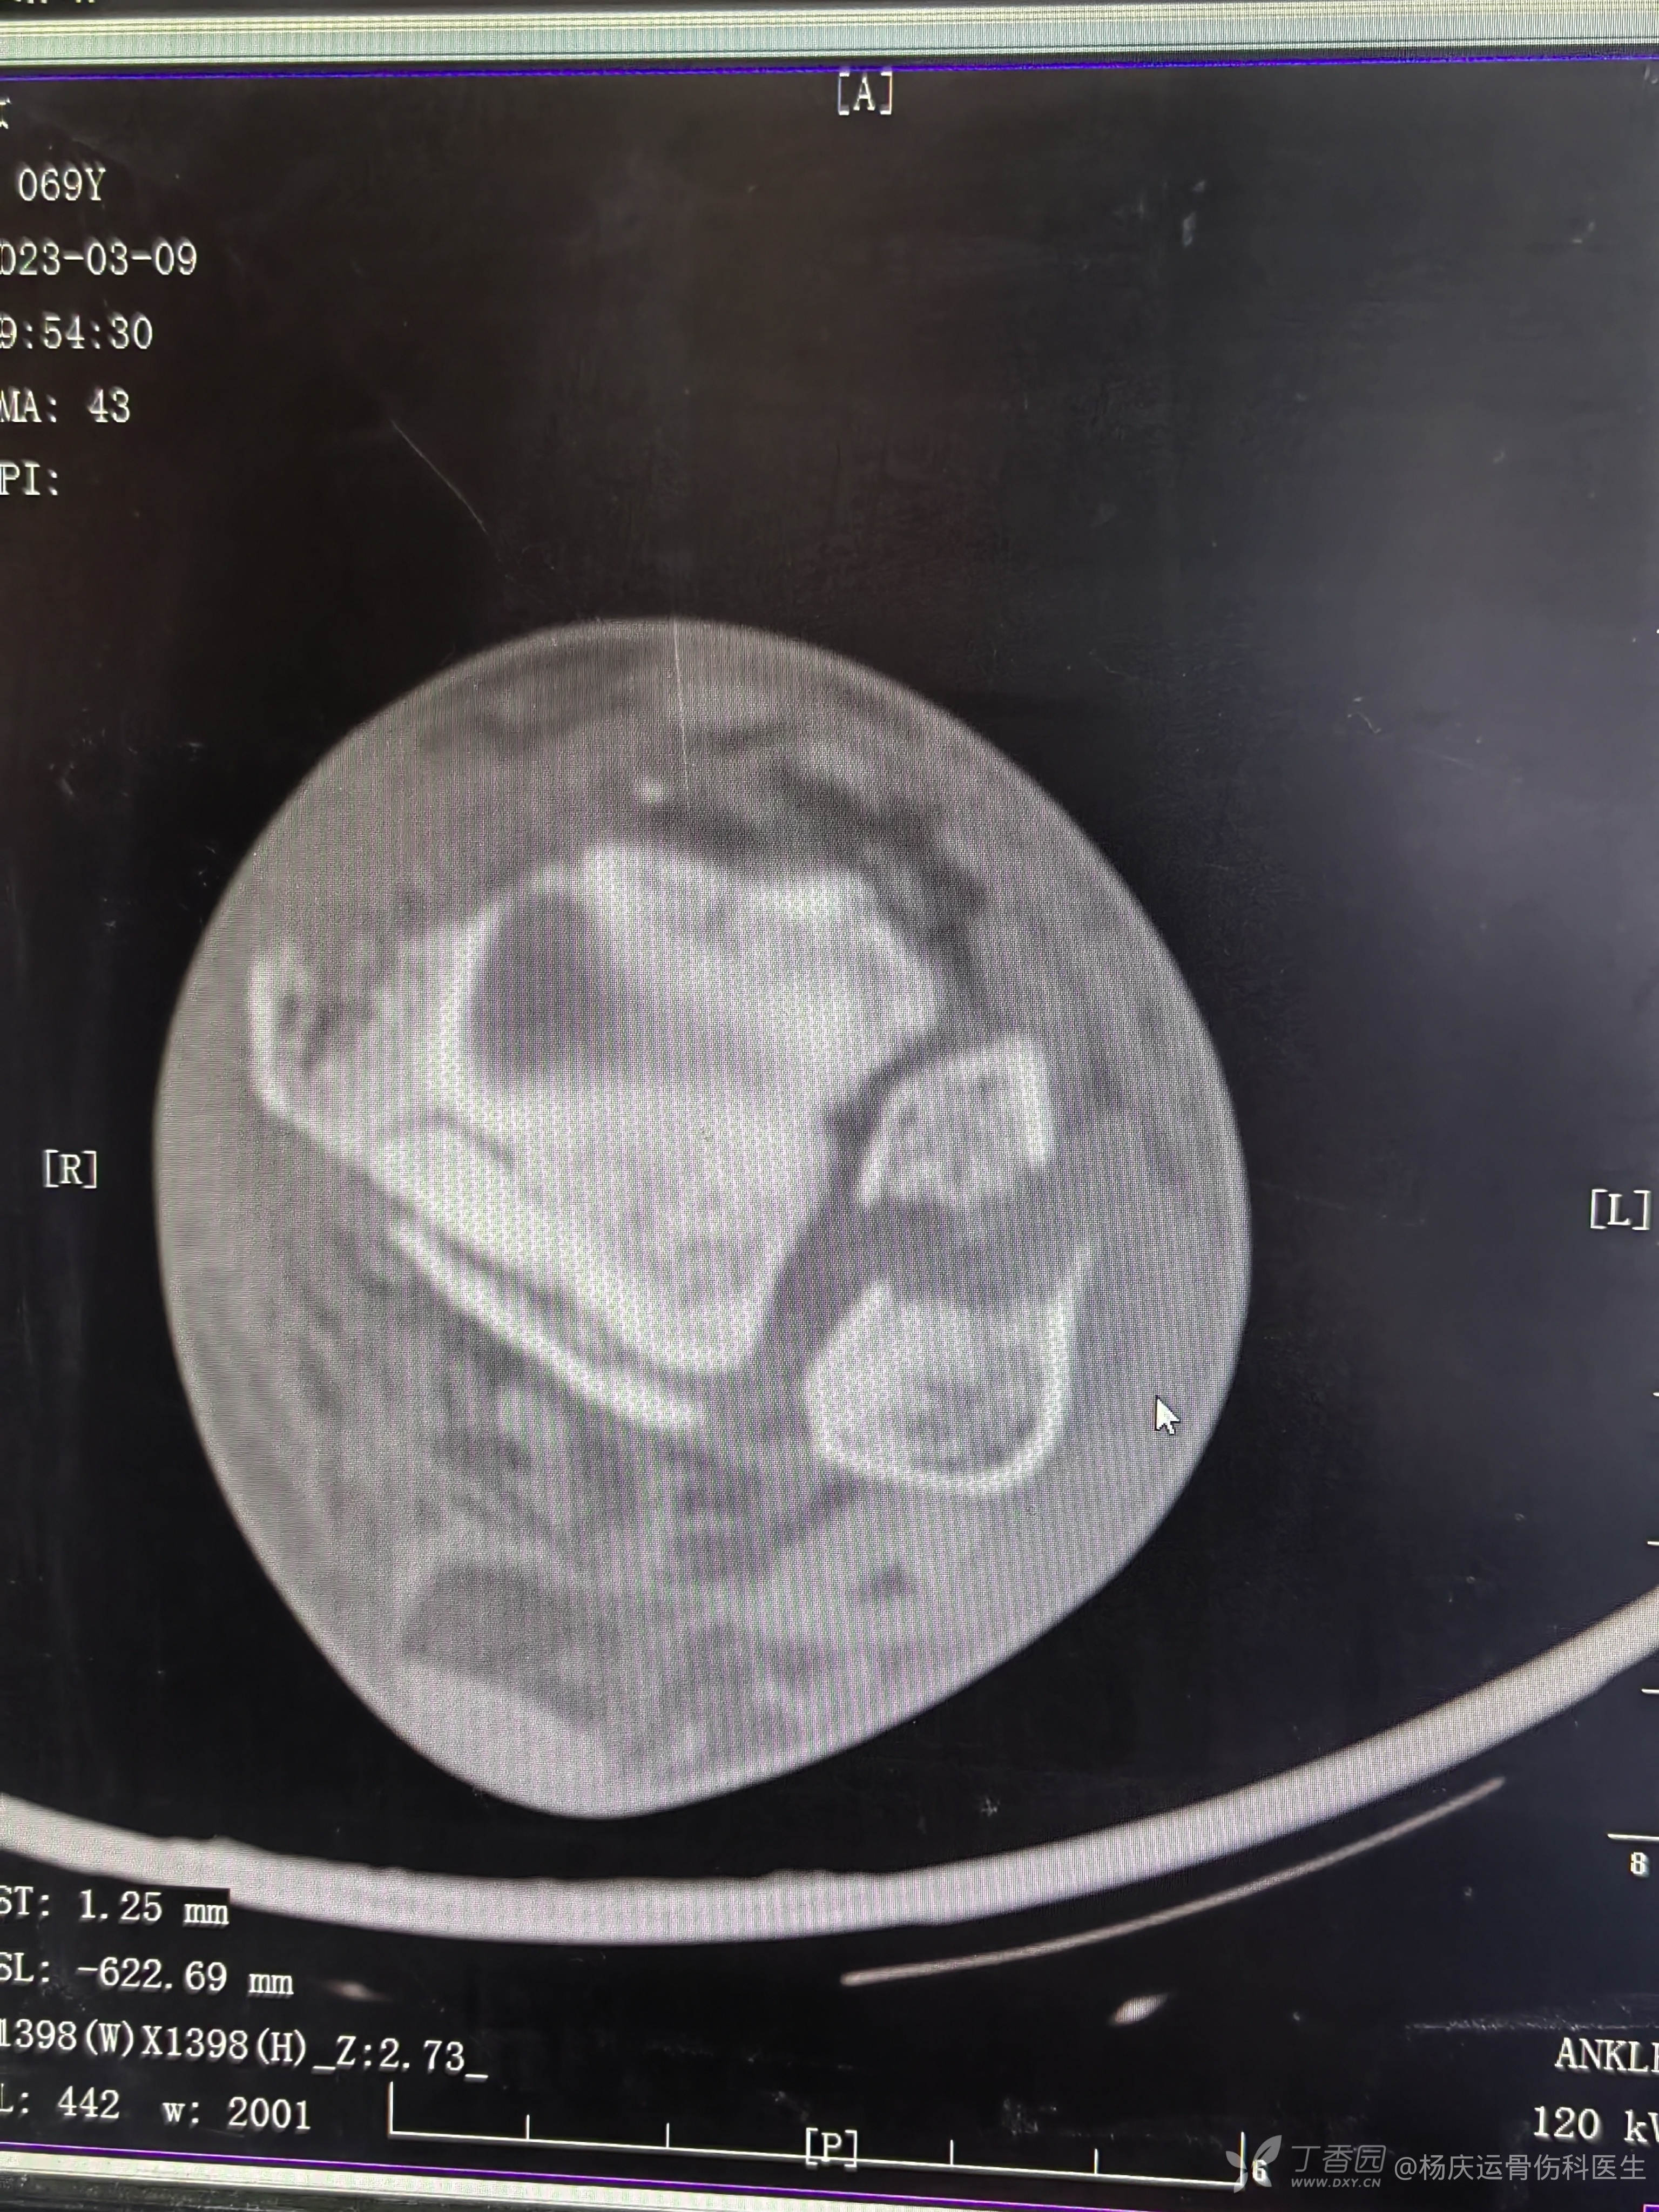

复位前CT